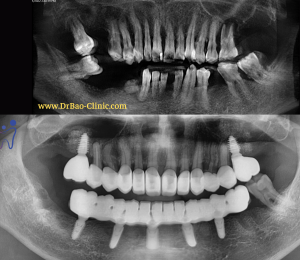

1/ The initial condition:

Functional assessment:

- Severe deep bite, occlusion

- Front lower teeth worn down

- Many porcelain crowns, bridge are broken, have not good contact

- Teeth No.23,24

4/ TREATMENT PROGRESSION:

- The fouth stage: full mouth rehalibitation and finish the implant treatment.